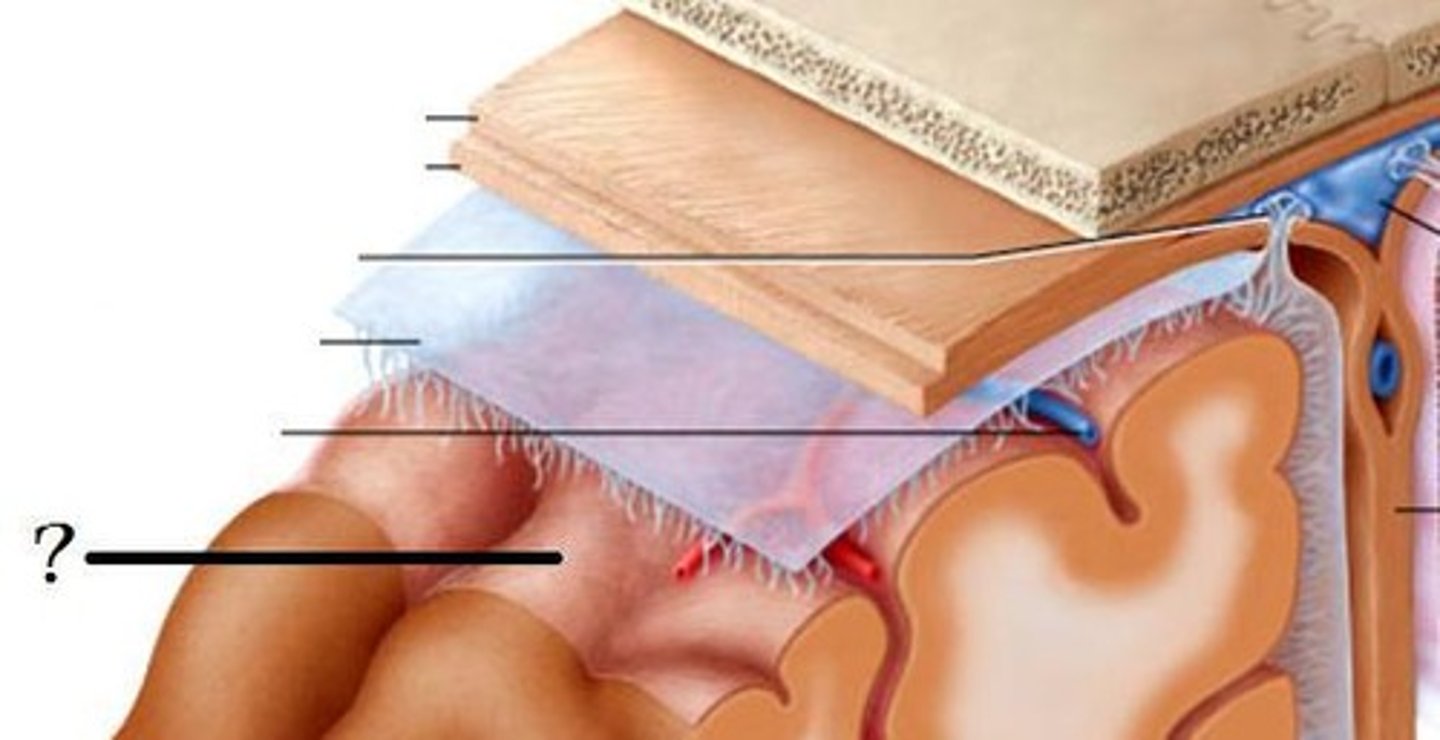

meninges function

protect brain and spinal cord

pia mater

deepest meninge, follows every contour of the brain

arachnoid mater

middle meninge, collagen and elastin fiber, spider web look

dura mater

made up of tough fibrous connective tissue, made up of the periosteal layer (creates periosteum of skull bone)

subarachnoid space

filled with cerebrospinal fluid

subdural space

below the dura mater

potential space (if you have a head injury

the blood goes into the subdural space)